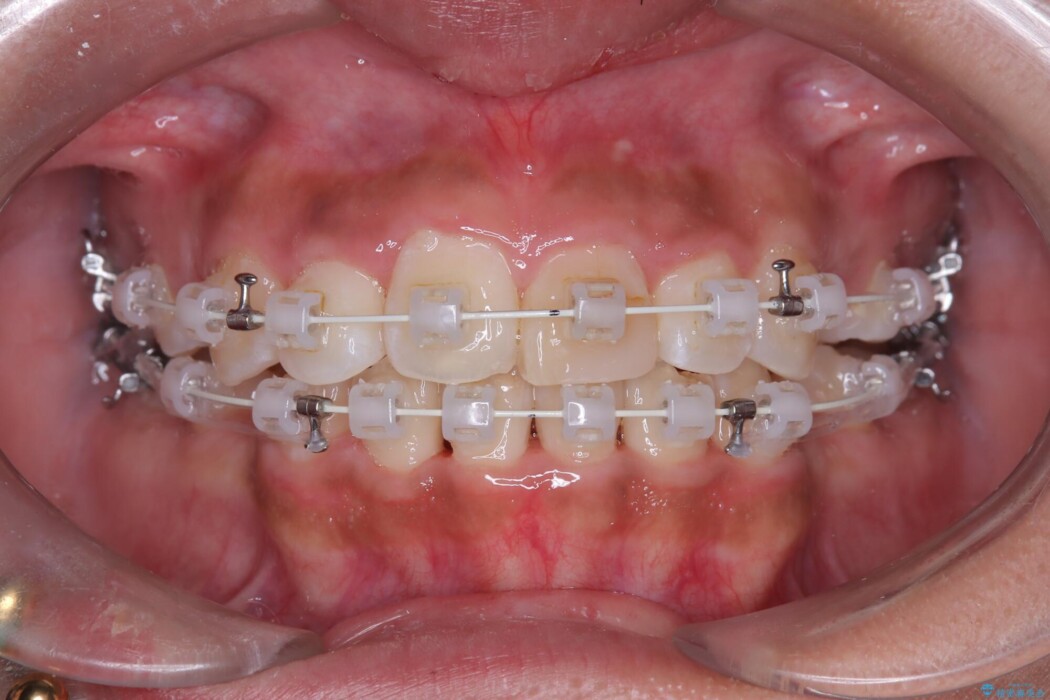

- 矯正装置:ワイヤー(審美装置)

無理に歯を並べても口元の突出感は解消されないため、上下左右4番を抜歯しスペースを確保、目立ちにくい審美ワイヤー装置にて治療を行うこととしました。

抜歯によって得たスペースを活用し、審美ワイヤーによる繊細な角度調整を行いながら前歯を後方へ移動。

突出していた口元のボリュームを段階的に抑制し、理想的なバランスへと導きました。